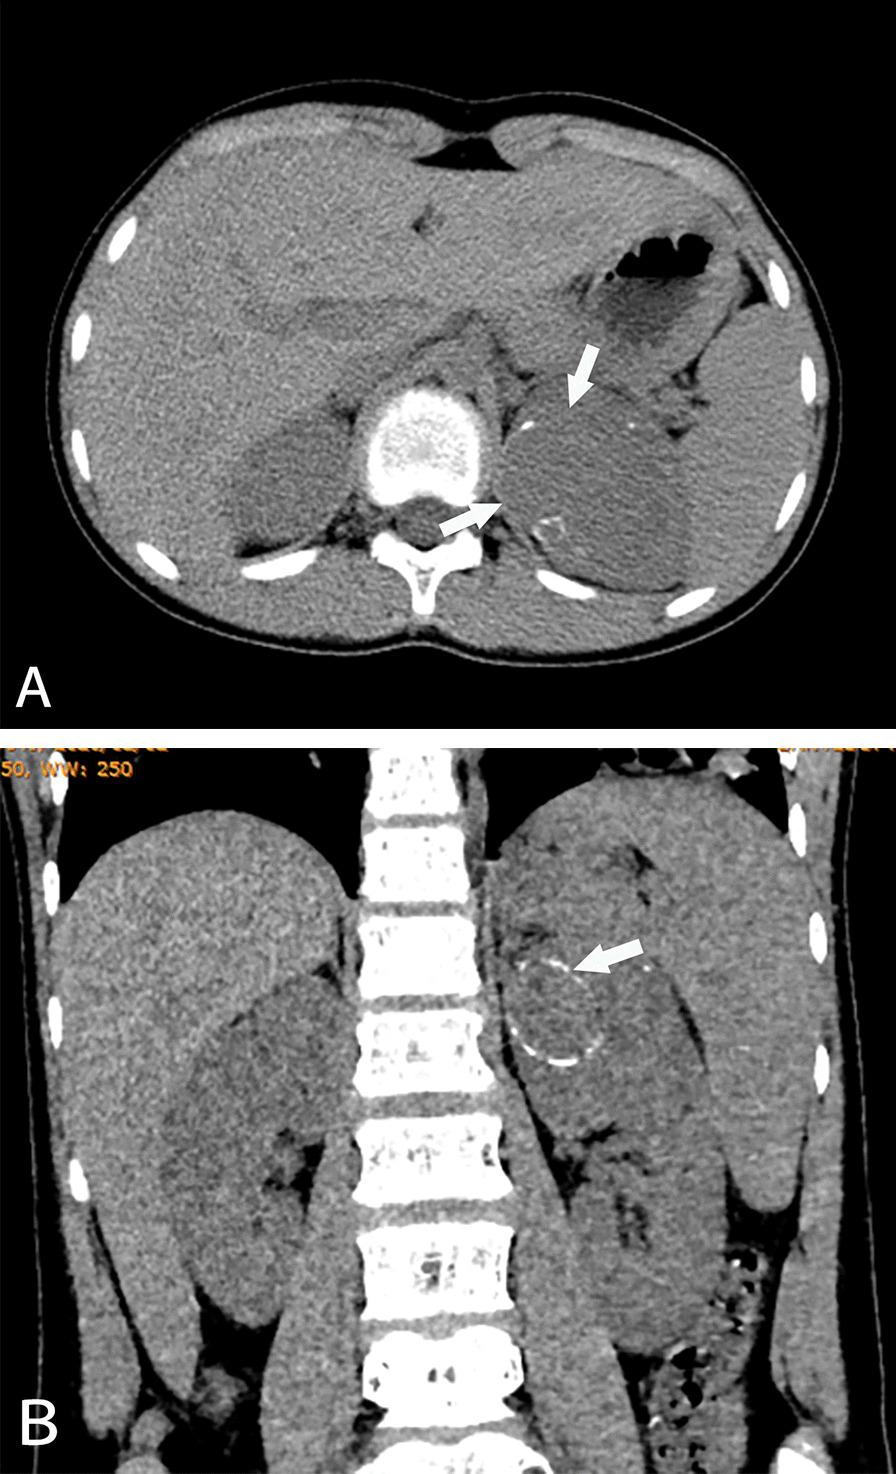

The study included CCSK (22 cases), MRTK (27 cases) and RCC (16 cases). There were no significant differences observed among the sex ratios of CCSK, MRTK and RCC (all P > 0.05). Among the three tumors, the onset age of MRTK patients was the smallest, while that of RCC patients was the largest (all P < 0.05). The tumor diameter of CCSK was larger than that of MRTK and RCC (all P < 0.001). For hemorrhage and necrosis, the proportion of MRTK patients was larger than that of the other two tumors (P = 0.017). For calcification in tumors, the proportion of calcification in RCC was highest (P = 0.009). Only MRTK showed subcapsular fluid (P < 0.001). In the arterial phase, the proportion of slight enhancement in RCC was lower than that in the other two tumors (P = 0.007), and the proportion of marked enhancement was the highest (P = 0.002). In the venous phase, the proportion of slight enhancement in RCC was lower than that in the other two tumors (P < 0.001). Only CCSK had bone metastasis. There was no liver and lung metastasis in RCC.

NWTs have their own imaging and clinical manifestations. CCSK can cause vertebral metastasis, MRTK can cause subcapsular effusion, and RCC tumor density is usually high and calcification. These diagnostic points can play a role in clinical diagnosis.